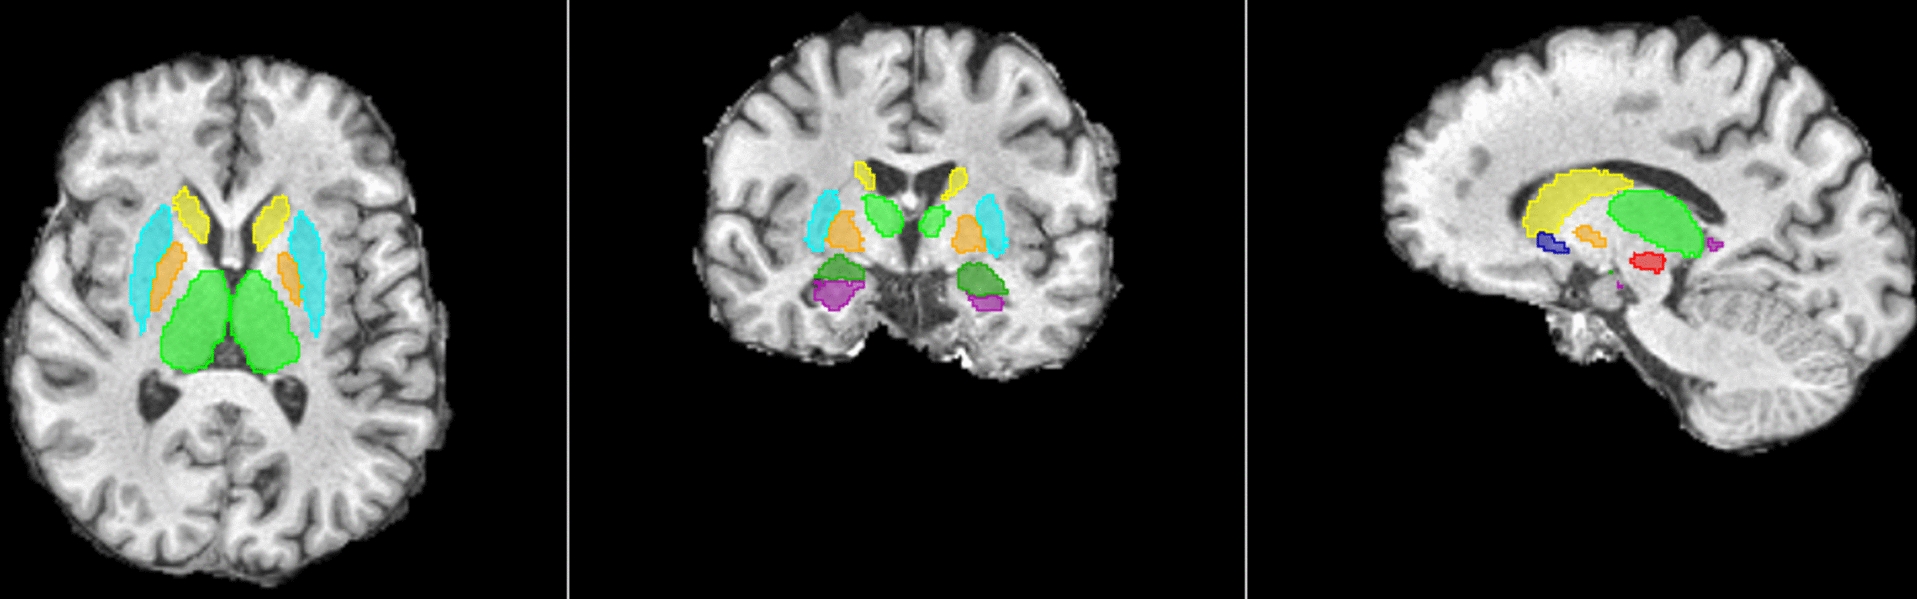

MDFNet: a multi-dimensional feature fusion model based on structural magnetic resonance imaging representations for brain age estimation

Brain age estimation plays a significant role in understanding the aging process and its relationship with neurodegenerati...

s2MRI-ADNet: an interpretable deep learning framework integrating Euclidean-graph representations of Alzheimer’s disease solely from structural MRI

To establish a multi-dimensional representation solely on structural MRI (sMRI) for early diagnosis of AD. A total of 3377...